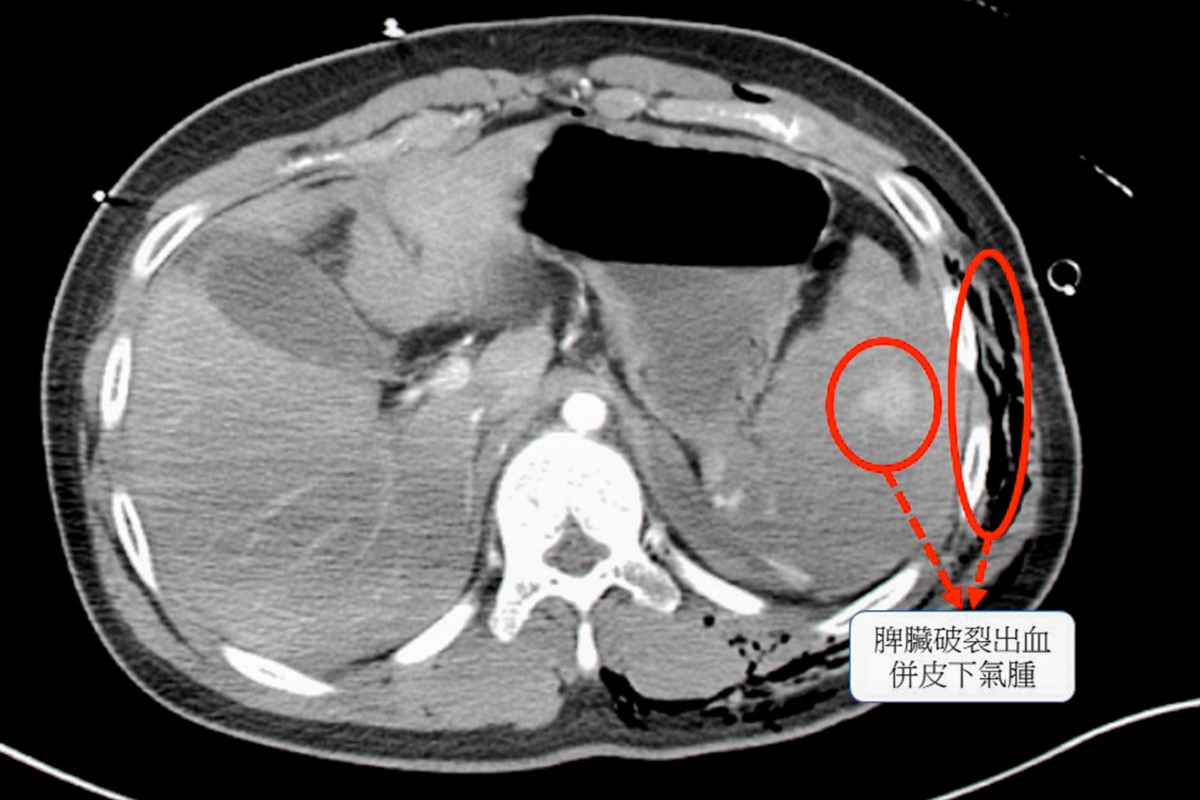

經過電腦斷層檢查,確認患者的脾臟已完全碎裂,是體內大出血的主因 ,同時合併胸腔積血、積氣,以及多處骨折與血管撕裂傷 。面對如此複雜的傷勢,外科團隊首先進行緊急手術,切除破裂的脾臟以控制出血 ;骨科與整形外科團隊則接力進行骨折固定與血管修補,成功穩定了患者的生命跡象 。